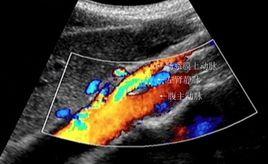

此病的診斷標準為:一側腎出血;尿紅細胞形態為非腎小球性;尿中鈣排泄是正常;膀胱鏡檢查為左側輸尿管口噴血或血性尿;腹部彩超或CT檢查員可見左腎靜脈擴張等。

超聲對胡桃夾綜合徵的診斷有著明顯的優勢,超聲檢查員時可清晰顯示腹主動脈,腸系膜上動脈及左腎靜脈的解剖情況,在不同橫斷面均可找到左腎靜脈擴張近段的最大內徑,測值準確,同時可觀察並測量腸系膜上動脈與腹主動脈夾角變化。彩超血流速度提供更準確的血流動力學變化,有助於此病診斷。超聲檢查還能除外先天性畸形,外傷,腫瘤,結石,感染性疾病及血管異常等腰三角形造成的血尿。